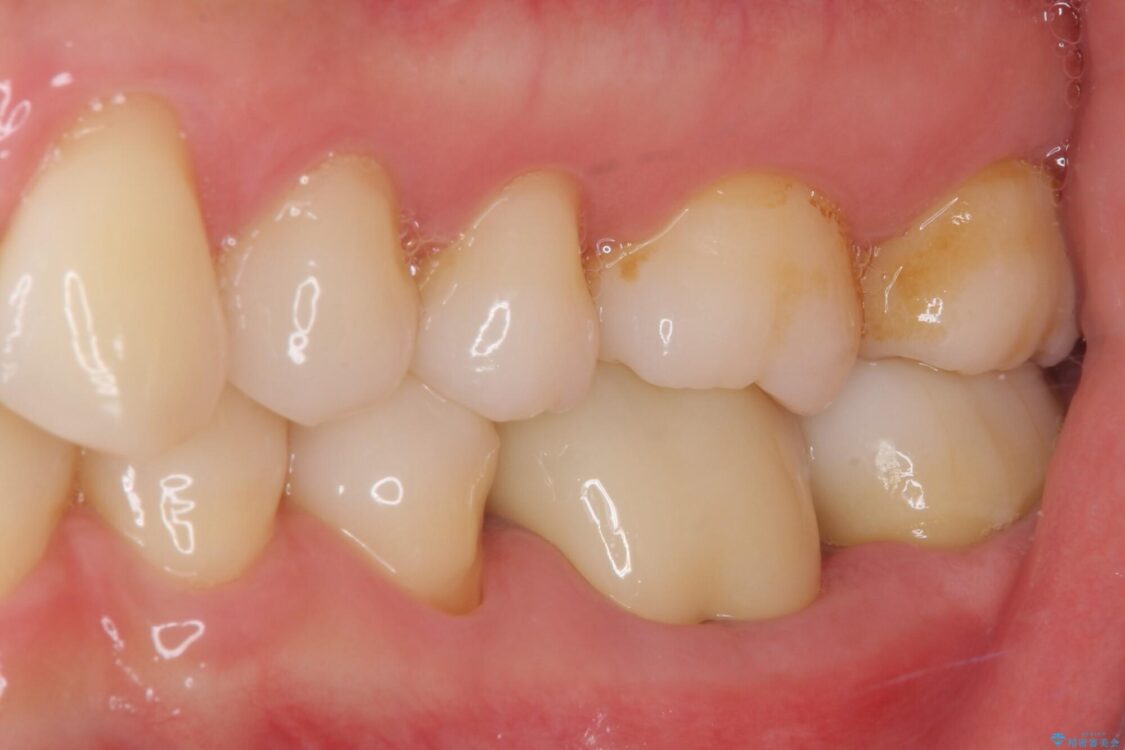

治療後

• むし歯で歯茎から血が出てくる オールセラミッククラウンでの補綴治療 治療後画像

術後6ヶ月でレントゲン写真を撮影したところ、出血の原因であった穴付近の溶けていた骨が回復している様子が認められました。